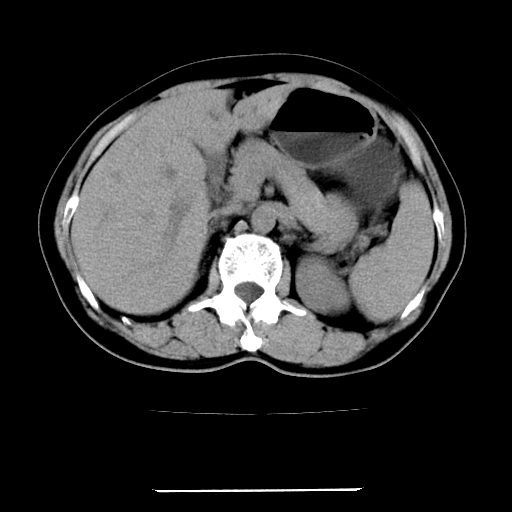

女,67岁,上腹部疼痛一周伴皮肤黄染,无发热。

左叶肝内胆管结石,并远端肝内胆管扩张。

肝内外胆管结石并肝内胆管扩张。

考虑肝胆管癌;胰头占位?【形态失常,体积增大】

1、肝门高密度影下层面和胰头层面可见轻度胆管扩张,而静脉和延迟期均未见扫描完胰头,不能完全排除胰头占位。2、肝门部高密度影,考虑钙化或结石。

考虑肝门胆管癌伴门脉左支受侵包埋,建议mrcp进一步检查。